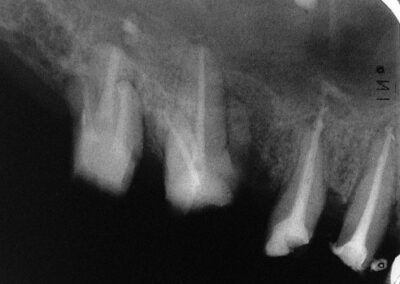

Über die Segnungen der sekundären Verlötung von Einzelkronen bei Bruxern und/oder im Grenzbereich der Zahnerhaltung in Hinsicht auf Funktion und Ästhetik haben wir ja schon früher ausführlich berichtet. Hier ein weiterer Fall aus dem Seitenzahnbereich: